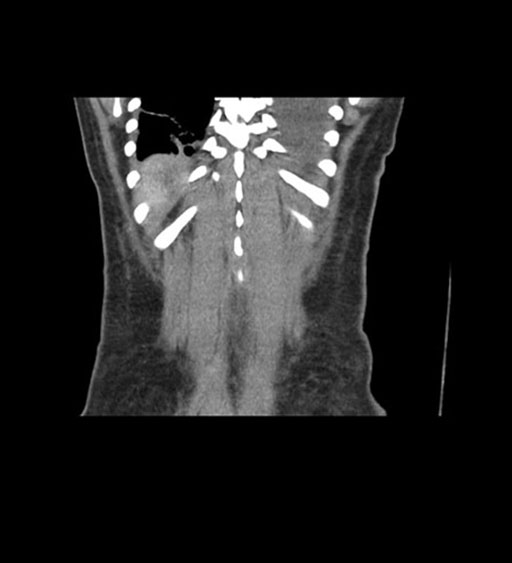

Coronal Arterial

Coronal Venous